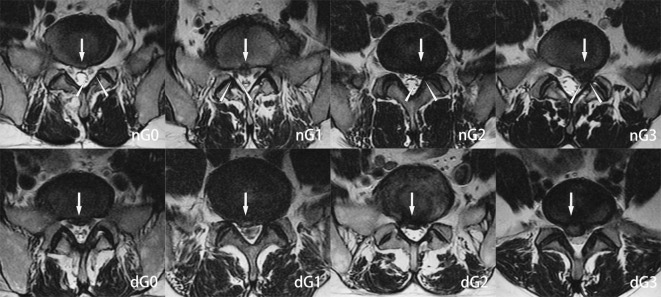

这是一项回顾性研究。本研究探讨经椎间孔入路联合椎间入路(PELD)的经皮内镜下腰椎间盘切除术治疗L4/5和L5/S1两节段椎间盘突出的效果是否不亚于后路腰椎椎间融合术(PLIF)。在这项回顾性研究中,我们纳入了40例L4/5和L5/S1两节段腰椎间盘突出症(LDH)患者,他们接受了PELD (n = 18)或PLIF (n = 22)。两组分为联合组(PELD)和融合组(PLIF)。联合组L4/5节段椎间盘突出采用椎间路入路,L5/S1节段椎间盘突出采用椎间路入路。术前采用MRI检查神经根及硬脑膜受压程度。采用视觉模拟评分(VAS)、Oswestry残疾指数(ODI)、日本骨科协会评分(JOA)和改良MacNab标准评价两组患者术前1周、3个月、6个月、12个月、24个月、36个月及术后最终随访的临床结局。两组患者术后不同时间点的VAS、ODI、JOA评分均较术前显著改善(P < 0.05)。综上所述,本研究旨在比较PELD和PLIF治疗L4/5和L5/S1双节段腰椎间盘突出症的疗效。与PLIF相比,PELD具有术中出血少、手术时间短、无需全身麻醉等优点。然而,PLIF术后复发的可能性较低。总之,两种方法都能给患者带来满意的效果。临床上,外科医生应仔细权衡两种手术的利弊,选择适合患者的手术方式。同时,在今后的研究中,我们应进一步延长随访时间,观察椎体融合术在预防术后复发方面是否更有优势。

This was a retrospective study. The present study investigates whether Percutaneous Endoscopic Lumbar Discectomy via Transforaminal Approach Combined with Interlaminar Approach(PELD) is no less effective than posterior lumbar interbody fusion(PLIF) in the treatment of L4/5 and L5/S1 two-level disc herniation. In this retrospective study, we included 40 patients with L4/5 and L5/S1 two-level lumbar disc herniation (LDH) who received PELD (n = 18) or PLIF (n = 22). The two groups are divided into a united group(PELD) and a fusion group(PLIF). In the united group, the transforaminal approach was adopted for L4/5 level disc herniation, and the interlaminar approach was adopted for L5/S1 level disc herniation. The degree of nerve root and dural compression determined by MRI was taken preoperatively. The clinical outcomes which preoperative 1 week, 3 months,6 months,12 months, 24 months, 36months and final follow-up after surgery between the two groups were evaluated using the visual analog scale (VAS), the Oswestry disability index (ODI), the Japanese Orthopaedic Association (JOA) and the modified MacNab criteria. In both groups, the VAS, ODI and JOA scores at different timepoints postoperatively were significantly improved compared with those preoperatively (P < 0.05). According to the modified MacNab criteria, the excellent or good outcome rate was 94.44% in the united group and 90.91% in the fusion group. Within 1 week after the operation, there was a significant difference in the improvement of clinical symptoms between the combination group and the fusion group (P < 0.05), and the combination group was better than the fusion group. Additionally, within three months postoperatively, the combination group exhibited significantly better functional improvements compared to the fusion group .With the gradual recovery of patients, there was no significant difference in the improvement of clinical symptoms between the two groups (P > 0.05). To sum up, This study aimed to compare the efficacy of PELD and PLIF in the treatment of dual-segmental lumbar disc herniation of L4/5 and L5/S1. Compared with PLIF, PELD has advantages in less intraoperative bleeding, shorter operation time and non-general anesthesia. However, the possibility of postoperative recurrence of PLIF is lower. In short, both methods can bring satisfactory results to patients. Clinically, surgeons should carefully weigh the advantages and disadvantages of the two operations and choose the operation method suitable for patients. At the same time, in future studies, we should further extend the follow-up time to observe whether vertebral fusion has more advantages in preventing postoperative recurrence.